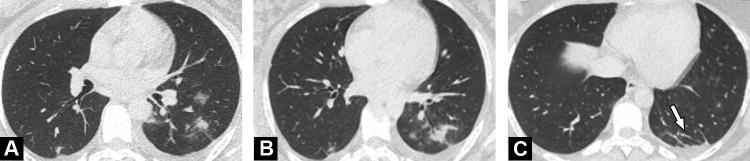

During the study period, among 205 diagnostic CT examinations, six examinations (6/205, 3%) in 6 different patients (4 men, 2 women; median age, 57 years) revealed images highly suggestive of COVID-19 pneumonia. The final diagnosis was confirmed by RT-PCR. Three inpatients were suspected of extra thoracic infection whereas three outpatients were either fully asymptomatic or presented with fatigue only. All had increased CRP serum level and lymphopenia. Disease extent on CT was mild to moderate in 5/6 patients (83%) and severe in 1/6 patient (17%).

Cumulative incidence of fortuitous diagnosis if COVID-19 pneumonia did not exceed 3% during the highest pandemic phase and was predominantly associated with limited lung involvement.